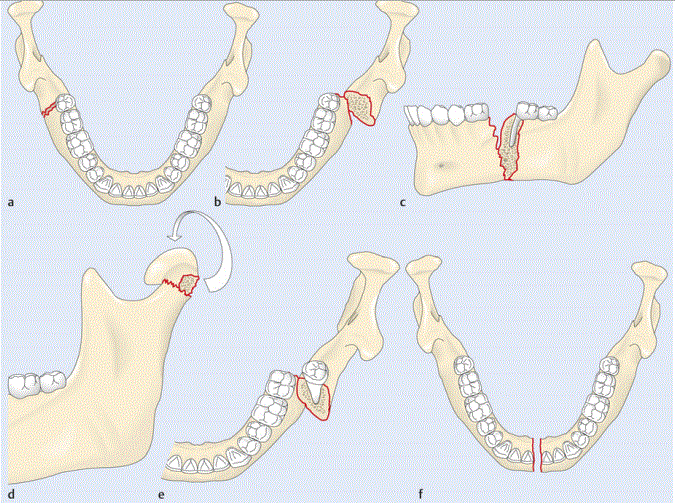

Beschreibe die Frakturmechanik folgender Bilder

Bild b) –> eine Kompressionsfraktur des Gelenkkopfes

Beschreibe die Dislokationsform des Unterkiefers

a –> sine dislocatione (keine Disloaktion)